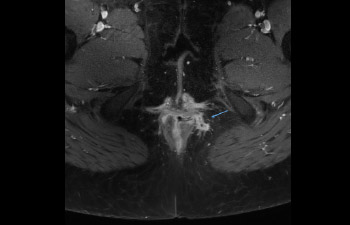

Pelvis with fistula

Pelvis image